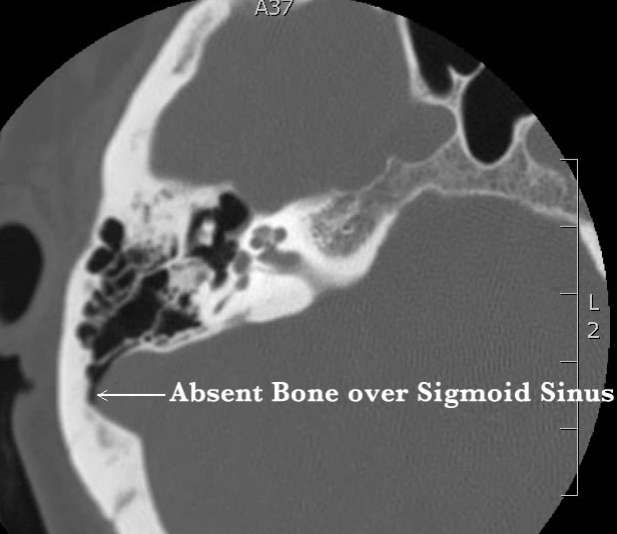

There are several radiographic imaging studies used to determine the cause of pulse-synchronous tinnitus. These studies include magnetic resonance imaging (MRI) of the brain, magnetic resonance angiography (MRA) of the brain and/or neck to evaluate arteries in the brain/neck, magnetic resonance venography (MRV) brain and/or neck for the venous system, CT temporal bones, CT angiography of the brain, and cerebral angiogram (similar to cardiac angiogram for the heart). Each of these imaging studies provides unique information. Which study, or studies, is/are used is determined by the possible cause for PST based on the individual’s history and physical exam. Sigmoid sinus dehiscence/diverticulum is best seen on a dedicated CT radiographic imaging of the ear and surrounding structures (CT temporal bones). The images below are examples of a normal sigmoid sinus (image on left) and sigmoid sinus dehiscence (image on right). [CT: White structures = bone; Black = air; Gray = soft tissue]